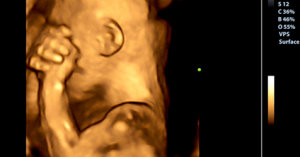

Ciò che prova il bambino nel ventre della madre è strettamente legato a ciò che le succede. In quel momento lei è il suo universo, il suo contatto più vicino con il mondo esterno e con il suo mondo interiore. Ma cosa prova il feto se la mamma piange?

La scienza ha dimostrato che durante la gravidanza il feto sente le stesse cose che sente la madre, con la stessa intensità. Se piangete per la tristezza, il vostro bambino sentirà questo stato emotivo sulla sua pelle, come se fosse suo.